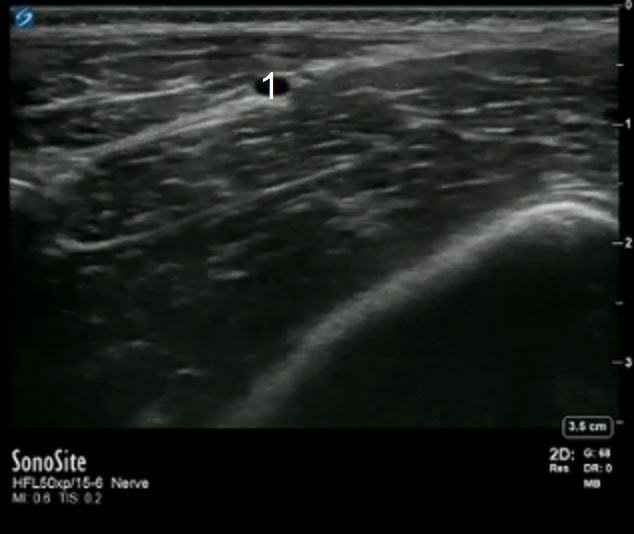

Fascia Iliaca Deep Circumflex Iliac Artery Image

Deep Circumflex Iliac Artery